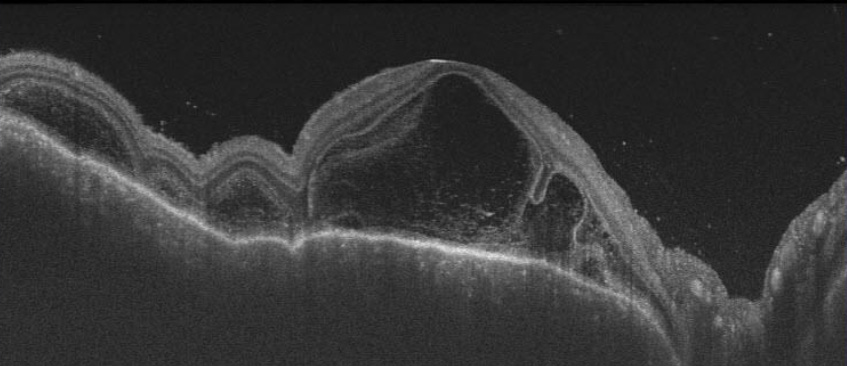

図1. 光干渉断層計の画像(フォークト・小柳・原田病)